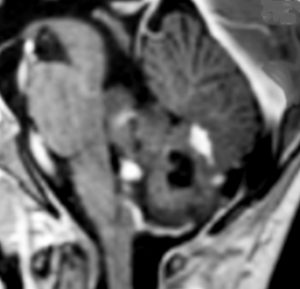

大脳皮質の毛様細胞性星細胞腫

小児期の右大脳頭頂葉にできた毛様細胞性星細胞腫です。小脳と同様に大脳にも壁在結節を作ってのう胞性増大する毛様細胞性星細胞腫というのはよくみかけます。てんかん(けいれん)発作で発症するものが多いです。腫瘍を摘出すると症候性てんかんが止まることが期待できます。治療方法は手術摘出です。腫瘍のある場所が深部で摘出術が神経脱落症状を招くと考えられる場合には,経過観察して,増大するようならガドリニウム増強される腫瘍実質部分にだけ,定位放射線治療することもあります。